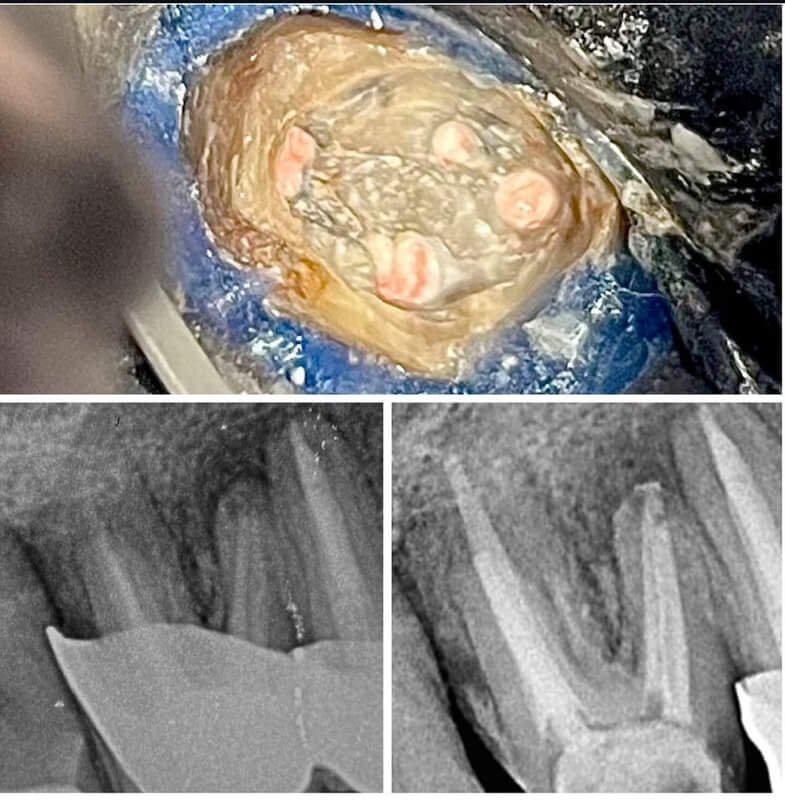

Endodonția este o ramură esențială a stomatologiei, axată pe diagnosticarea, prevenirea și tratamentul afecțiunilor pulpei dentare și a țesuturilor periapicale. Această specialitate joacă un rol crucial în salvarea dinților naturali, evitând extracțiile și menținând sănătatea orală pe termen lung. Prin tehnici avansate și echipamente de ultimă generație, endodonția asigură tratamente precise și eficiente, contribuind la redarea sănătății și funcționalității dinților într-un mod durabil și predictibil.

Utilizarea tehnicilor moderne asigură un tratament rapid, precis și confortabil pentru pacient.